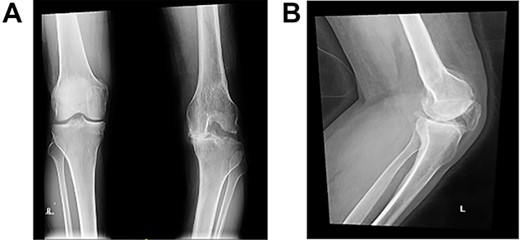

At the 2-year follow-up visit, the patient’s active ROM continued to be between 4 and 85° (Fig. 7). Patient’s functional outcome score was measured using the Knee Injury and Osteoarthritis Outcome Score pre- and post-operatively, with marked improvement in scores noted from 45 to 76%.

Post-operative plain radiographs at 2-year follow-up visit; (A) 2-year post-operative AP radiograph showing implant in place with decreased lateral gap sized to be 1.57; (B) 2-year post-operative lateral radiograph of the knee showing implant in a satisfactory position.